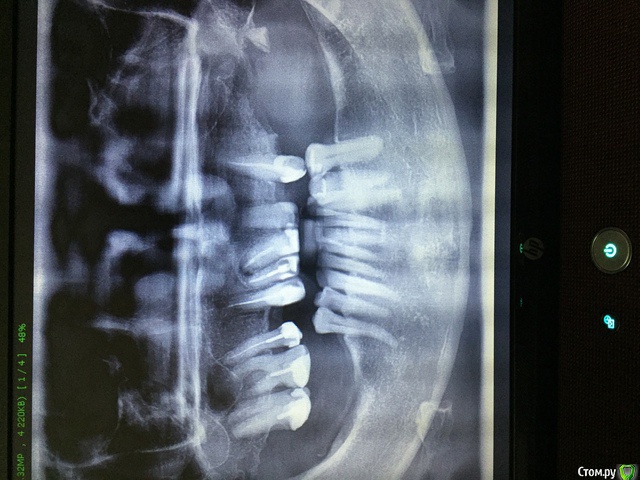

Olga40 Опубликовано 10 апреля, 2019 Поделиться Опубликовано 10 апреля, 2019 (изменено) Добрый день! Уже два года постоянный насморк, у лора была проблемы не видит. Подскажите, пожалуйста может ли это быть связано с зубами? И можно ли как то спасти и какие зубы? Или все таки полное протезирование? Прошу прощения, фото перевернуть не получается Изменено 10 апреля, 2019 пользователем Olga40 Ссылка на комментарий